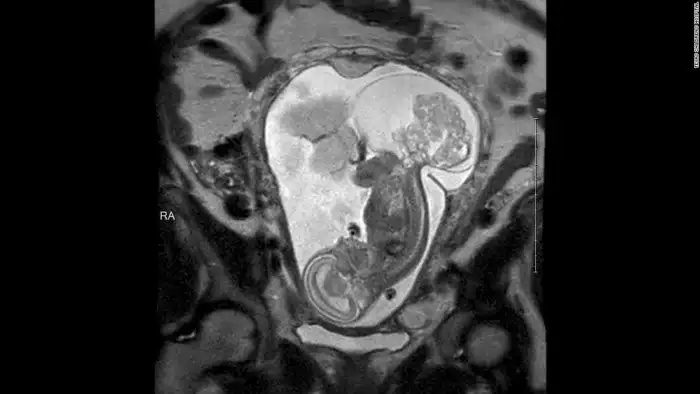

На снимке видна опухоль, угрожающая жизни Линли.